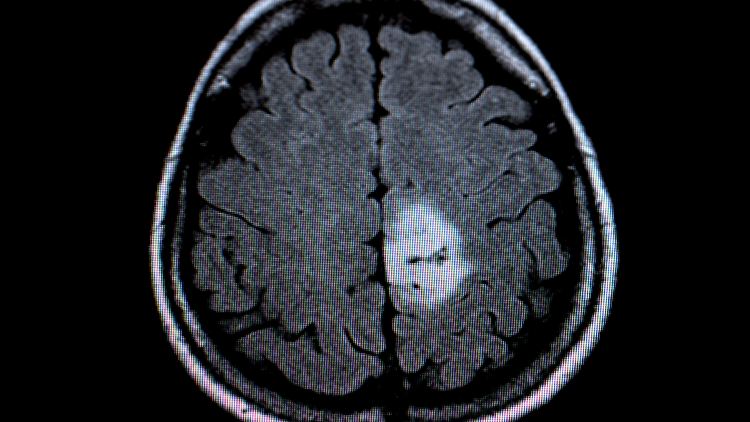

MRT-Bild des Gehirntumors (heller Fleck).

(Foto: dpa)